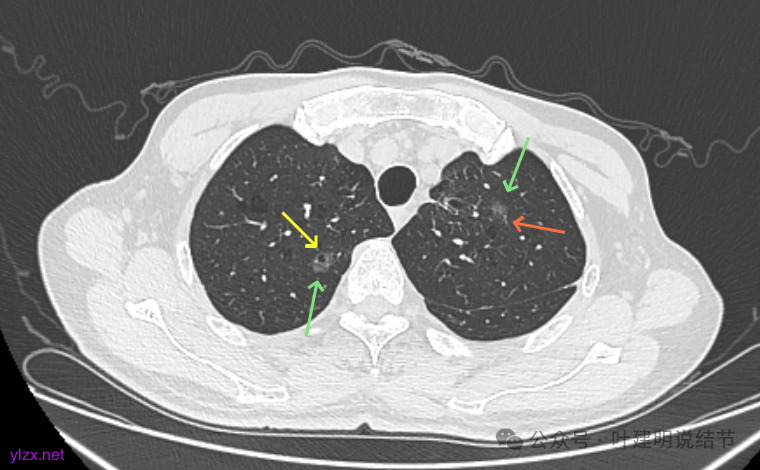

再看2022年9月的:

右上病灶此层面偏长条,密度较低。

左上已经手术。

左上另有一处磨玻璃结节,由于手术后结构变化,此灶是术前哪处感觉不太好对比。

再看2024年9月复查的:

右上的仍小而淡,轮廓仍是清楚的。

左上的病灶略显模糊,密度不太纯,较前相仿。